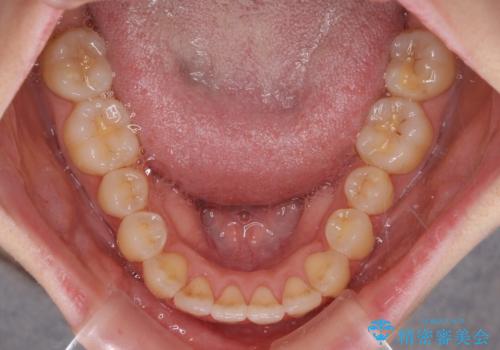

気になるデコボコとオープンバイト インビザラインでの矯正治療

- 前歯のデコボコと上下が開いていることを気にして来院された患者様です。

いわゆるオープンバイトは、インビザラインによる治療が適しているため、インビザラインにて治療を行うこととしました。

オープンバイトは容易に後戻りを起こすため、少しでも後戻りリスクを軽減するために舌癖改善のトレーニングをしっかりと行っていただきました。